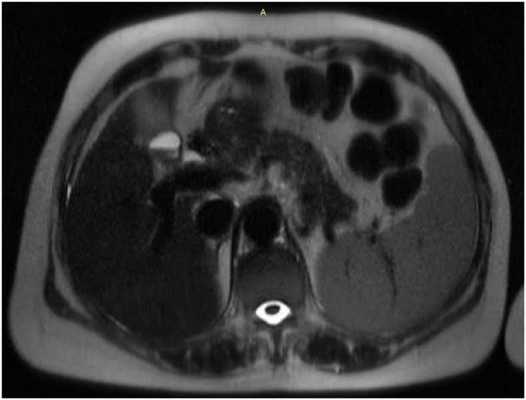

![МРТ брюшной полости]()

МРТ брюшной полости. На МР-томограмме в аксиальной плоскости отмечается увеличение размеров селезенки, МР-сигнал от селезенки однородный, структура селезенки не изменена (серый МР-сигнал на представленном изображении справа).